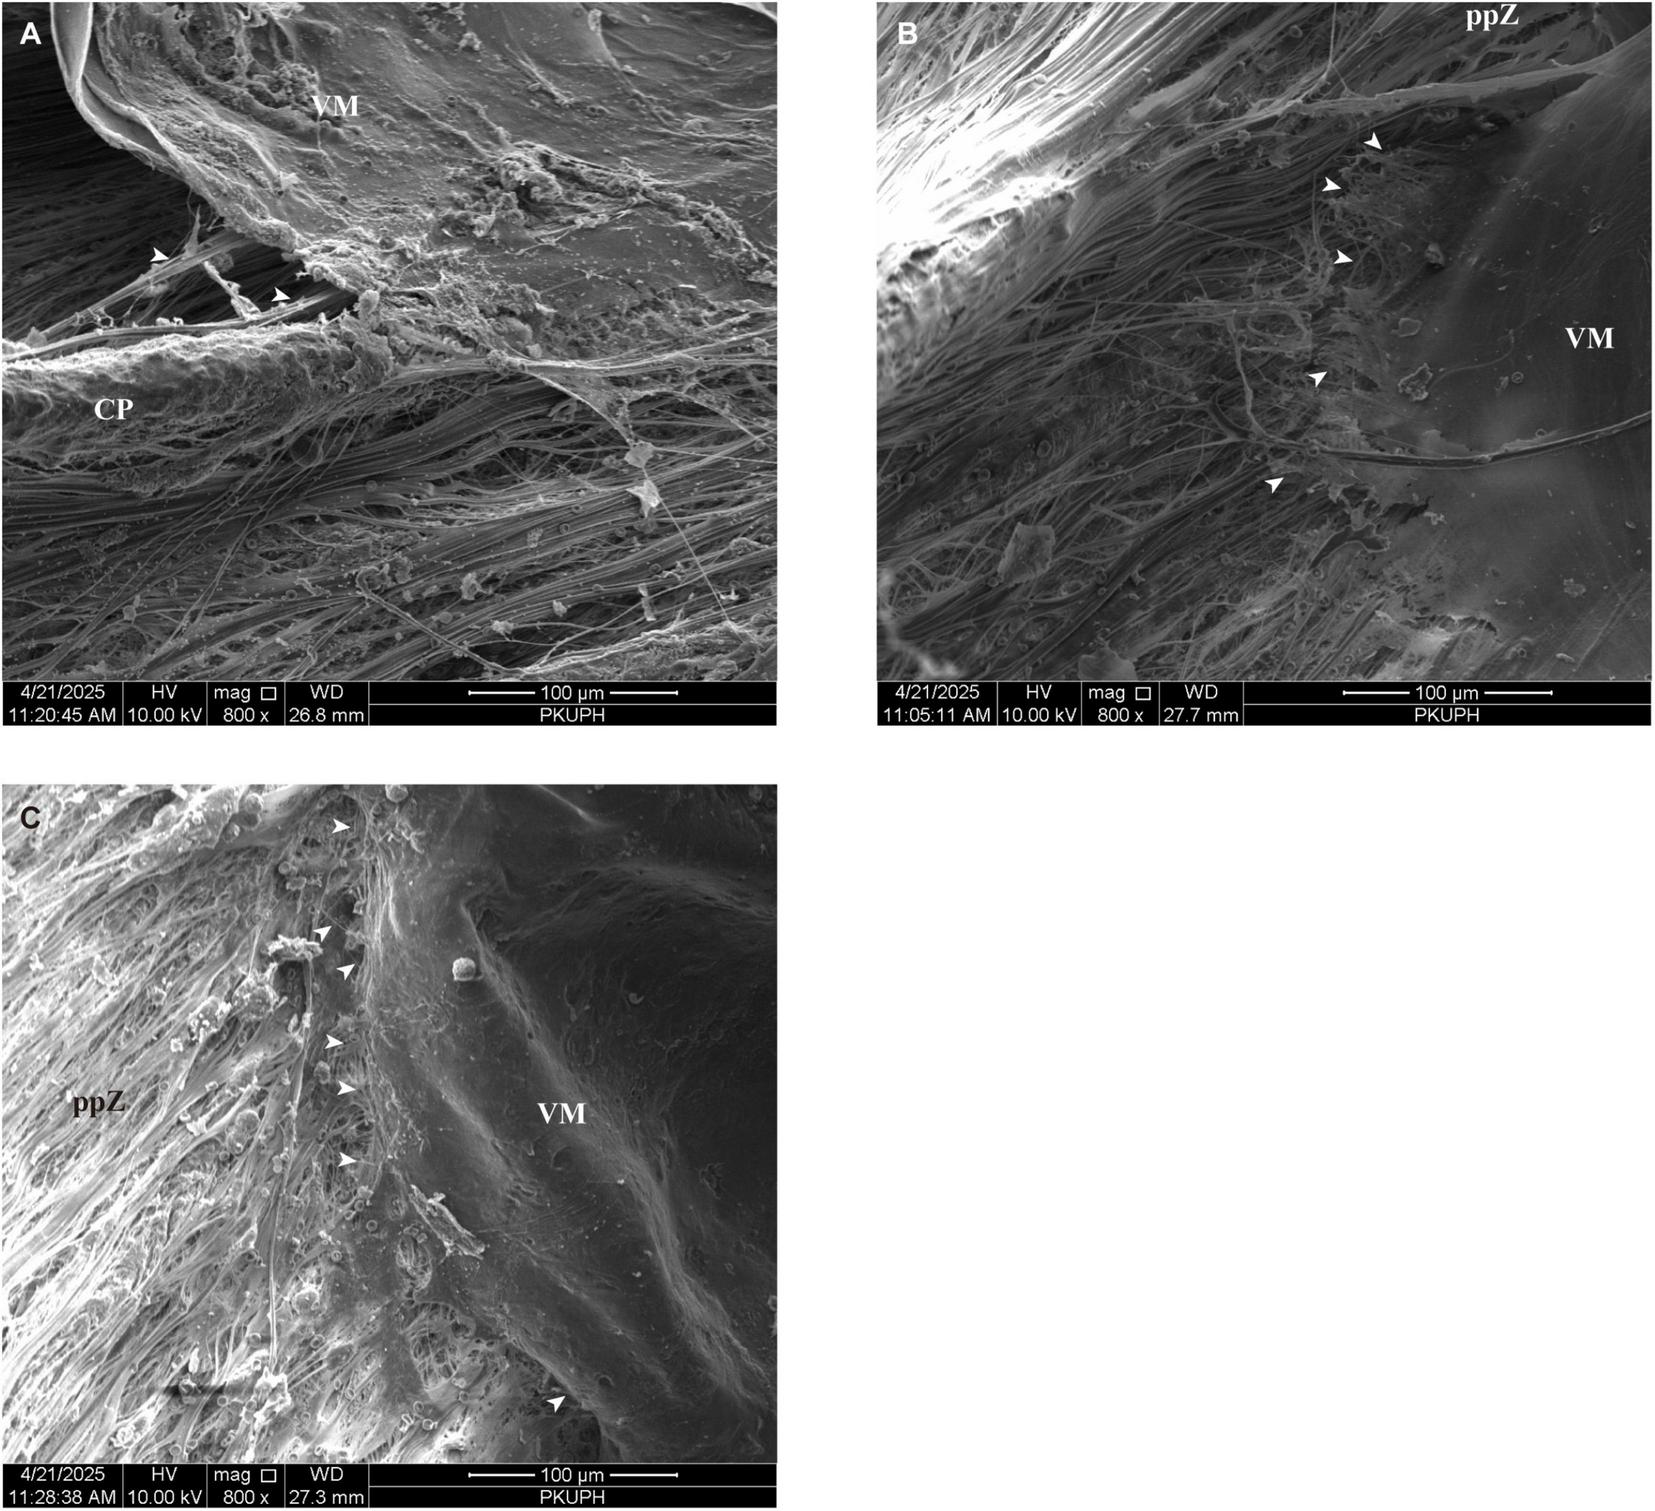

3.4 Canine zonule system

The zonular apparatus in canine eyes demonstrates anatomical and microscopic characteristics that closely mirror those of felines (Figures 8A–C). Similar to the feline configuration, canine eyes possess both major and intermediate CPs (Figure 8B), a feature absent in porcine iridociliary anatomy. As illustrated in Figures 8B,C, zonule fibers originate from both the crests of CPs as well as the valleys between them, subsequently projecting toward the lens capsule. An anterior view of the lens further reveals that zonular fibers consolidate into larger bundles at distances of approximately 0.26–0.5 mm posterior to the anterior edge of the CPs before inserting into the lens capsule (Figure 8A).

(A) Scanning electron microscopy reveals the anatomical features of the lens and ciliary body in a canine sagittal section. An anterior view of the lens demonstrates that zonular fibers consolidate into larger bundles at distances of approximately 0.26–0.5 mm posterior to the anterior edge of the ciliary processes before inserting into the lens capsule (B) Similar to the feline configuration, canine eyes possess both major and intermediate ciliary processes. (C) Zonule fibers originate from both the crests of ciliary processes and the valleys between them, subsequently projecting toward the lens capsule. (D) When viewed from the posterior aspect of the lens, the anterior vitreous zonules (blue arrow) are situated in a distinct anatomical plane, separate from the primary lens zonular apparatus (white arrow). This spatial arrangement closely parallels that observed in porcine eyes, where the anterior vitreous zonule insert into the lens capsule at similarly positioned sites near the lens equator. (E) Further dissection of the vitreous membrane, extending to the posterior portion of the ciliary processes, reveals the presence of intermediate vitreous zonules (white arrows). The canine intermediate vitreous zonule establish fibrous connections with the pars plana zonules. These interconnections exhibit reciprocal weaving, resulting in an intricate reticular network. (F) This reticular fiber arrangement (white arrows) overlies both the crestal ridges and inter-process valleys of canine ciliary processes. CP, ciliary process; L, lens; mCP, major ciliary processes; iCP, intermediate ciliary process; ppZ, pars plana zonule; VM, vitreous membrane, Z, zonule.

When viewed from the posterior aspect of the lens, the aVZ are situated in a distinct anatomical plane, separate from the primary lens zonular apparatus. The spacing of aVZ ranged from 13 to 35 μm, with an average value of approximately 25.77 μm. This spatial arrangement closely parallels that observed in porcine eyes, where the aVZ insert into the lens capsule at similarly positioned sites near the lens equator (Figure 8D). Within this region, clearly defined interfascicular spaces are found between the VM and the CPs.

Further dissection of the VM, extending to the posterior portion of the CPs, reveals the presence of iVZ. Consistent with findings in porcine and feline eyes, the canine iVZ establish fibrous connections with the pars plana zonules. These interconnections exhibit reciprocal weaving, resulting in an intricate reticular network (Figures 8E,F). As observed in other species, this reticular fiber arrangement overlies both the crestal ridges and inter-process valleys of canine CPs (Figures 8E,F). Additionally, canine eyes display continuous fibrous connections between the VM and the iVZ, mirroring the architecture described in porcine and feline specimens (Figure 9A). These iVZ bundles are irregularly spaced around the posterior pars plicata and pars plana at intervals of approximately 32.62μm (ranged from 15.7 to 48.26 μm).

FIGURE 9

(A) Canine eyes display continuous fibrous connections between the vitreous membrane and intermediate vitreous zonules (white arrows). (B) Upon dissection of the vitreous membrane from the pars plana to the ora serrata, the posterior vitreous zonules (white arrows) form elaborate interconnections with pars plana zonules. (C) Posterior vitreous zonules (white arrows) exhibit an orthogonally interwoven configuration, thereby establishing a complex fibrous matrix. CP, ciliary process; ppZ, pars plana zonule; VM, vitreous membrane.

Upon dissection of the VM from the pars plana to the ora serrata, the pVZ form elaborate interconnections with pars plana zonules (Figure 9B). These fibers exhibit an orthogonally interwoven configuration, thereby establishing a complex fibrous matrix (Figure 9C). The porosity of pVZ was measured at 20.95%. As shown in Table 1, the variations in the ocular suspensory zonule system among humans, pigs, cats, and dogs are summarized.